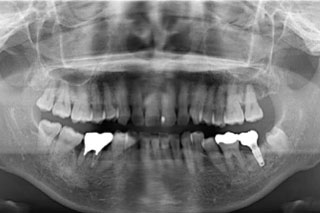

初診時のパノラマレントゲン写真です。

左下の奥歯の骨が全周吸収してしまっており、保存不可能な状態でした。インプラントを埋入していくにあたり、骨が全くなかったのでまずはGBR(骨造成)を行いました。

右下の被せ物が入っている歯は骨が部分的に吸収してしまっており、将来的に隣の歯まで骨が吸収してきてしまう可能性をお伝えすると、抜歯をしてインプラントをしていくことになりました。